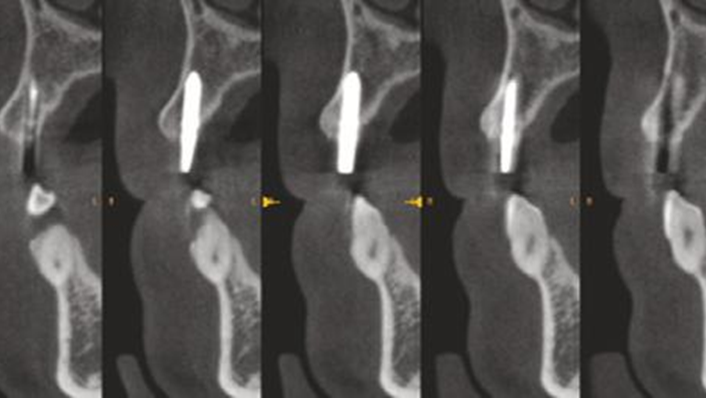

Clinical case: Patient-centered approach: treatment strategy for Root Membrane Technique & delayed implant placement

- Courtesy of Dr. Yoshiharu Hayashi, Japan -

Socket Shield Technique, anterior esthetics, maxillary anterior, esthetic, esthetics, delayed implant placement, socket preservation, AnyRidge, Root Membrane Kit, Root Membrane Technique, Partial Extraction Therapy, PET, esthetic zone, fuse abutment, Dr. Yoshiharu Hayashi,#11,#21,#22

AnyRidge implant system, fuse abutment Root membrane kit, PET Kit